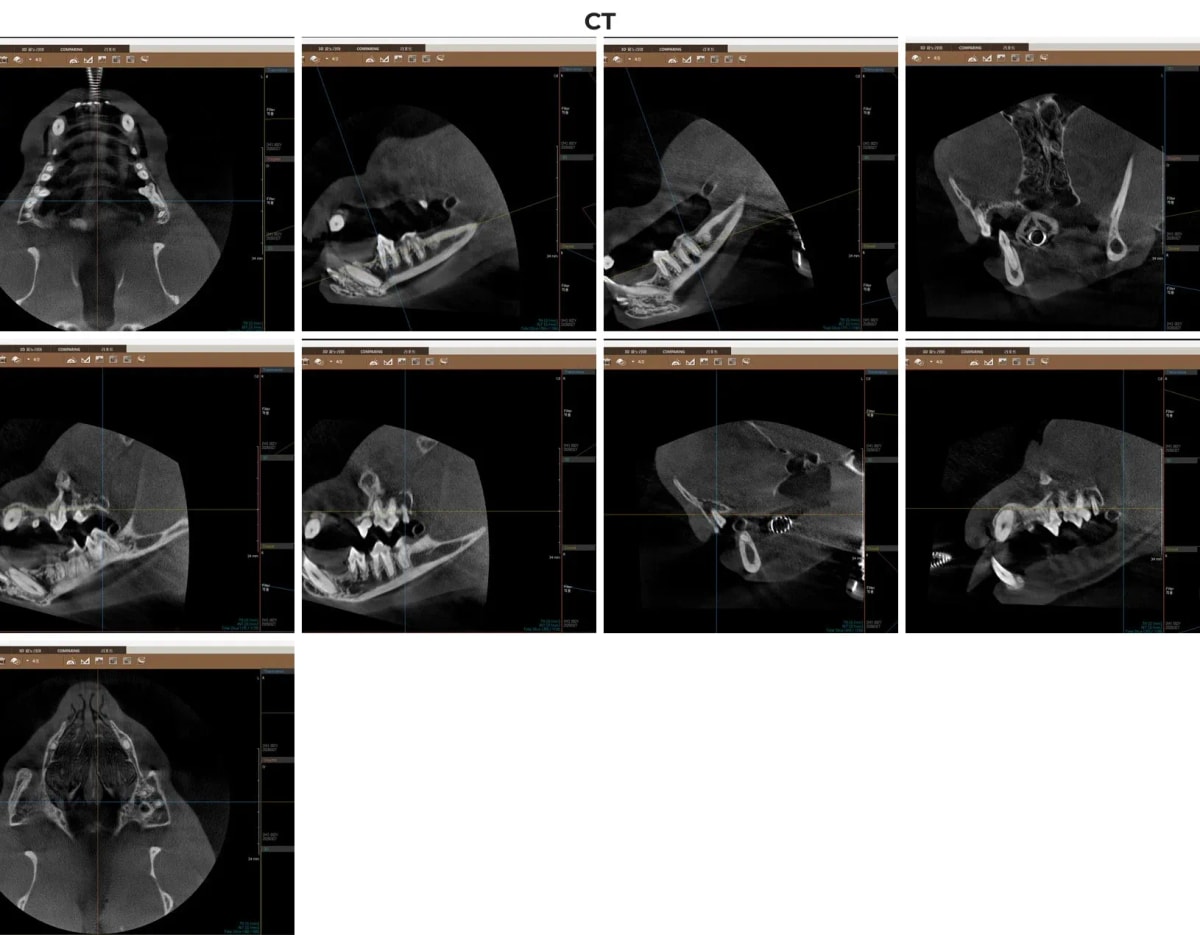

2. 광주 전남 유일 동물전용 치과 CT 진단

겉으로 보이는 잇몸 염증만으로는 치아 뿌리와 치조골(잇몸뼈가 녹는 현상)의 정확한 손상 정도를 파악하기 어렵습니다. 무조건적인 전체 발치를 피하고 살릴 수 있는 치아를 선별하기 위해서는 3차원 영상 장비가 필수적입니다.

광주 금호동물병원은 광주·전남 유일의 동물전용 치과 CT를 보유하고 있습니다. 일반 엑스레이로는 중첩되어 보이지 않는 미세한 치근 분기부 뼈 소실이나 숨은 병변을 0.1mm 단위로 정확히 찾아내어, 꼭 필요한 치아만 발치하는 '맞춤형 보존 치료'를 가능하게 합니다.

고양이 치아 뿌리 상태를 정밀하게 보여주는 치과 전용 CT 영상 소견